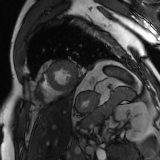

Refer to caption

Figure 2: Examples of tracking results using the proposed method (MPN-C). From left column to right: ED frame, ES frame, warped frame from ED, overlay of ES frame and the warped mask, and estimated motion field using HSV color coding. The color coding wheel legend indicates the motion directions.